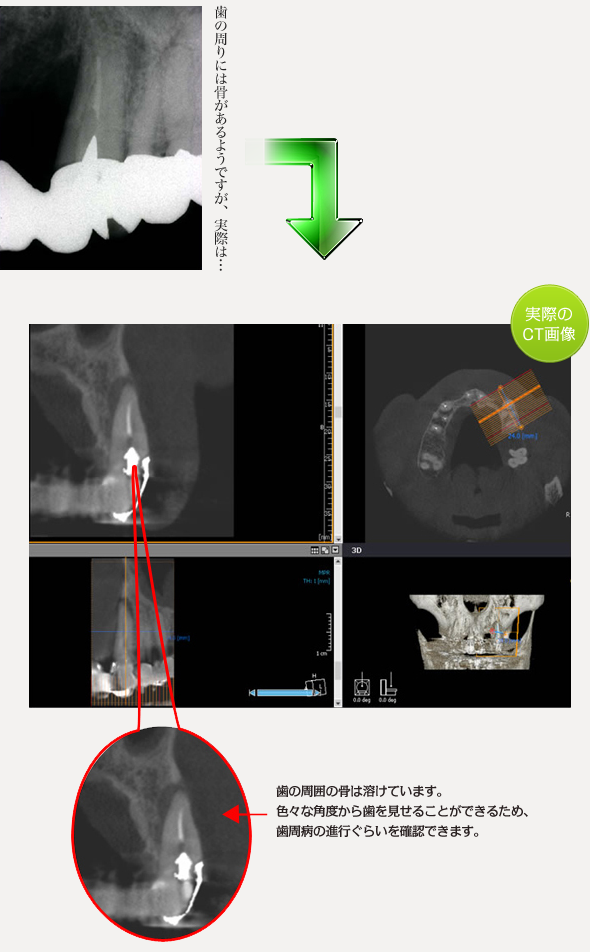

歯周病

様々な症状にて実際のCTで撮影したものをご確認ください。